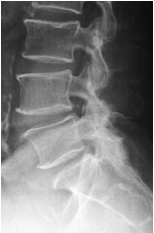

The X Rays of the lumbosacral spine showed lumbar spondylosis. There was no spondylolysis or spondylolisthesis.